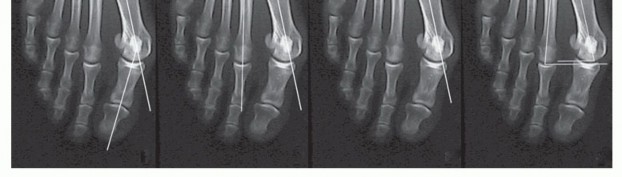

The sesamoid position is determined by its relationship with the first metatarsal diaphyseal axis. Typically, the sesamoids remain in their anatomic position; with progressive hallux valgus deformity, the first metatarsal head progressively subluxates medially in relation to the sesamoids.

Normal (grade 0) sesamoid position: The tibial and fibular sesamoids are equidistant from the bisecting line of the first metatarsal.

Sesamoid position grades 1 to 3: Grades 1 through 3 signify an increasingly greater lateral position of the tibial sesamoid relative to the bisecting line of the tibial shaft axis, with grade 3 indicating that the tibial sesamoid is positioned completely lateral to the reference line (FIGS 1C and 2).

FIG 1 • AP radiograph of a patient with hallux valgus. Left, HVA (up to 15 degrees). Second from left, first IMA (up to 9 degrees). Second from right, sesamoid position. In this patient, the tibial sesamoid is divided into two halves by the diaphyseal axis of the first metatarsal, which means the beginning of a grade 2

sesamoid subluxation (normal is grade 0). Right, relative length of the first and second metatarsals; normal is up to 5 mm.

FIG 2 • Evaluation of hallucal sesamoid position. Grade 0, no displacement of sesamoids relative to the middle diaphyseal axis of the first metatarsal (normal). Grade 1, overlap of less than 50% of the tibial (medial) sesamoid to the reference line. Grade 2, overlap of more than 50% of the tibial sesamoid to the reference line. Grade 3, tibial sesamoid completely displaced beyond the reference line.